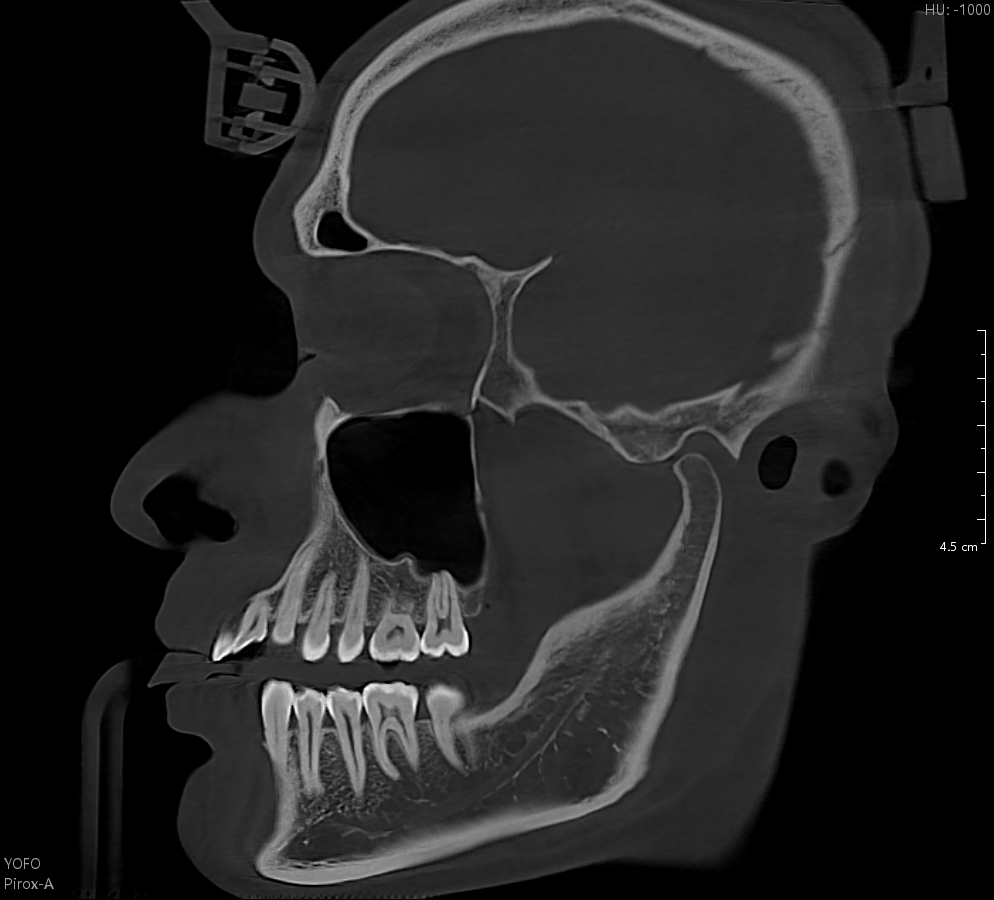

24x21cm超大视野 轻松总览完整颌面

有方Pirox-A在成像视野方面“更上一层楼”,最大24x21cm的成像视野,轻松总览口腔领面全局状况。更有16x13cm和5x5cm视野范围可选,满足不同临床需求。